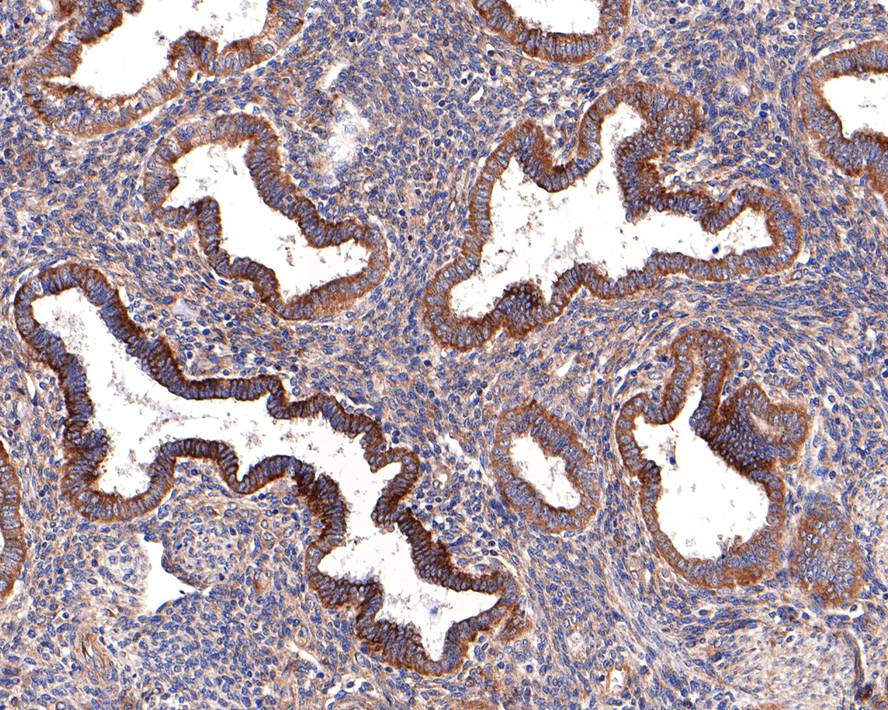

Immunohistochemical analysis of paraffin-embedded human endometrium tissue with Rabbit anti-CD39 antibody (ET1704-74) at 1/400 dilution.

The section was pre-treated using heat mediated antigen retrieval with Tris-EDTA buffer (pH 9.0) for 20 minutes. The tissues were blocked in 1% BSA for 20 minutes at room temperature, washed with ddH2O and PBS, and then probed with the primary antibody (ET1704-74) at 1/400 dilution for 1 hour at room temperature. The detection was performed using an HRP conjugated compact polymer system. DAB was used as the chromogen. Tissues were counterstained with hematoxylin and mounted with DPX.